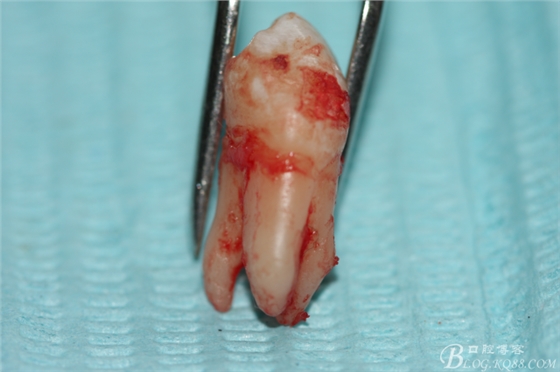

6.下頜離體第一前磨牙牙根形態(tài)